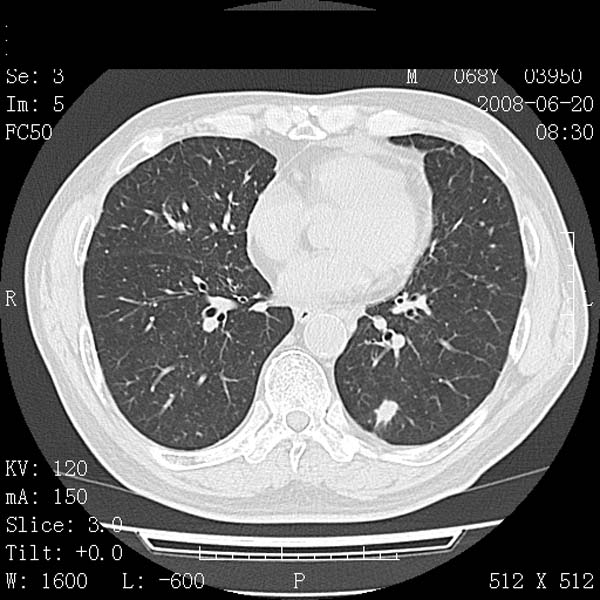

以下是引用守望可可西里在2008-6-24 1:11:00的发言:[br][br] 考虑为周围型肺癌:[br] 1.分叶结节,形态极不规则,蟹足样伸展的恶性浸润特征比较明确。[br] 2.磨玻璃影中由多个更高密度小结节聚集呈梅花瓣样。[br] 3.局部胸膜凹陷征比较明确。[br][br] 另:纵隔胸膜明显增厚、粘连。

以下是引用zjzjr在2008-6-24 11:19:00的发言:[br]支持左下肺周围型肺癌伴右肺转移,纵隔淋巴结转移,心包积液.

以下是引用zhangling在2008-6-24 14:56:00的发言:[br]我们科室意见报告为[br][br]1考虑左下肺周围型肺癌[br]2右肺小结节考虑转移瘤,纵隔淋巴结转移[br]3心包积液. [br] 各位老师分析的相当好 谢意[br]